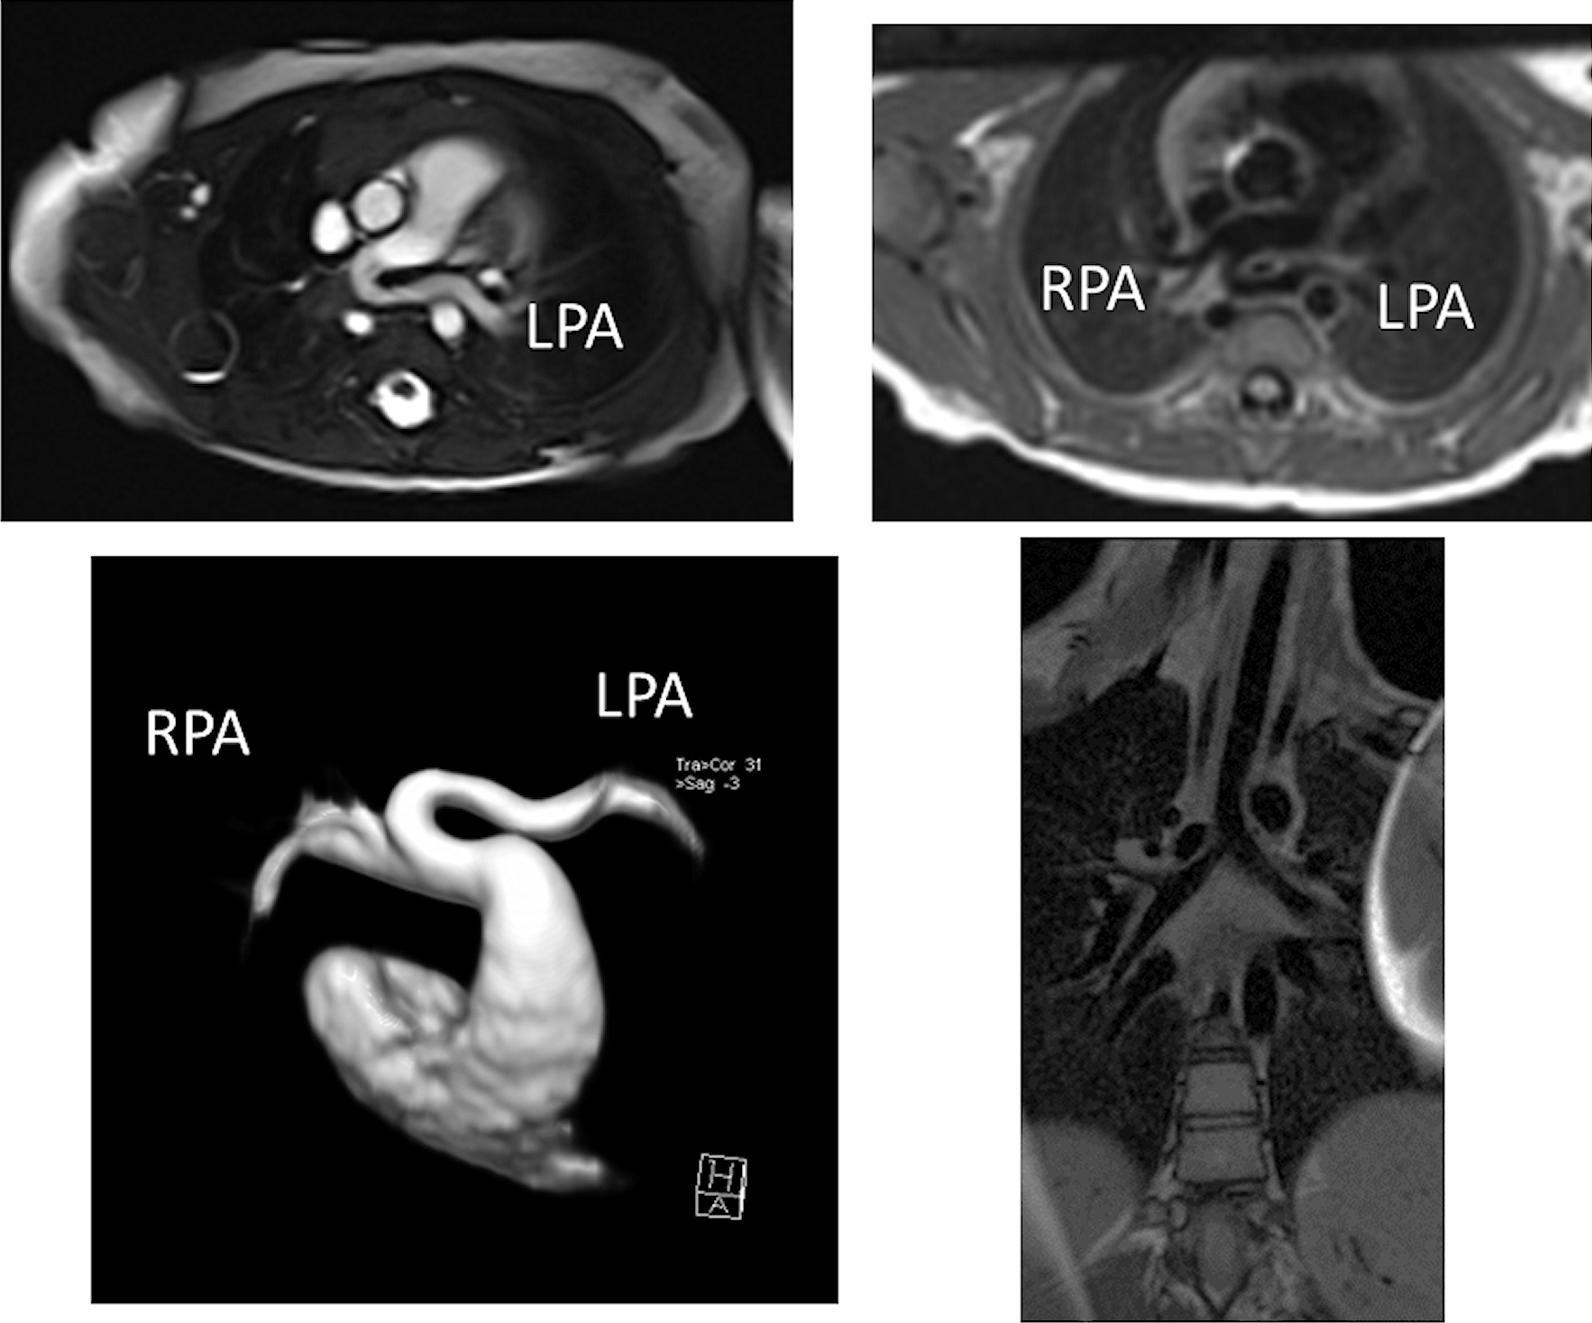

Cardiovascular magnetic resonance (CMR) has been utilized in the management and care of pediatric patients for nearly 40 years. It has evolved to become an invaluable tool in the assessment of the littlest of hearts for diagnosis, pre-interventional management and follow-up care. Although mentioned in a number of consensus and guidelines documents, an up-to-date, large, stand-alone guidance work for the use of CMR in pediatric congenital 36 and acquired 35 heart disease endorsed by numerous Societies involved in the care of these children is lacking. This guidelines document outlines the use of CMR in this patient population for a significant number of heart lesions in this age group and although admittedly, is not an exhaustive treatment, it does deal with an expansive list of many common clinical issues encountered in daily practice.

心血管磁共振(CMR)在儿科患者的管理和护理中已经应用了近 40 年。它已经发展成为评估最小的心脏的宝贵工具,用于诊断、介入前管理和随访。尽管在许多共识和指南文件中提到,但在儿科先天性心脏病和后天性心脏病领域,目前还缺乏一份由众多参与儿童护理的学会共同认可的、最新的、独立的、针对 CMR 使用的大型指南。本指南文件概述了 CMR 在该年龄段的许多心脏病变中的应用,尽管不能说是详尽的治疗方法,但它确实涉及了在日常实践中经常遇到的许多常见临床问题的广泛列表。